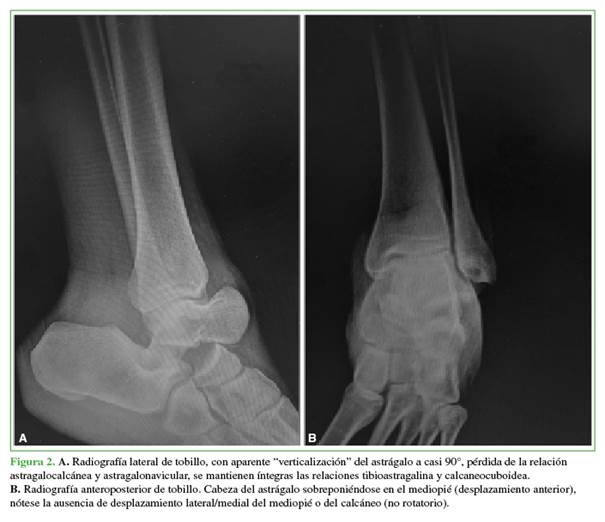

Se tomaron radiografías anteroposterior y lateral de tobillo que mostraron la pérdida de la relación articular del astrágalo con luxación astragalocalcánea posterior, luxación astragalonavicular con preservación de las relaciones articulares tibioastragalina y calcaneocuboidea sin fractura del cuello del astrágalo. La tomografía computarizada como estudio complementario no reveló lesiones asociadas no evidentes (Figuras 2 y 3).